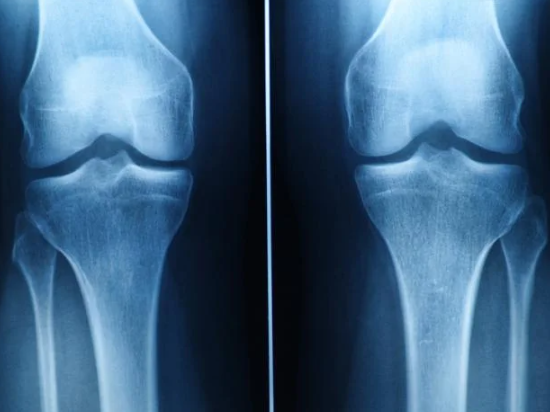

**무릎 연골 찢어짐 치료**는 손상의 위치, 크기, 증상 정도에 따라 접근 방법이 달라집니다. 병원에서는 MRI 등의 영상검사를 통해 상태를 정확히 파악할 수 있으며, 다양한 보존적 또는 수술적 치료법이 존재합니다.

병원 진료 시 활용되는 검사

MRI 검사는 연골 손상의 위치와 범위를 파악하는 데 유용합니다. 실제로 제 지인은 무릎이 자주 붓는 증상으로 병원을 찾았다가 연골 찢어짐을 진단받았습니다.